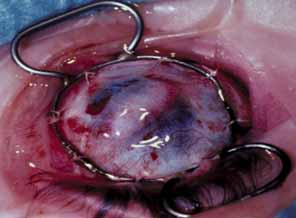

KERATOPLASTY IN INFANTS WITH OPAQUE CORNEAS

Lens involvement can include corneolenticular adhesion, corneolenticular contact, or cataract. In cases in which the lens is involved, vitreoretinal and systemic abnormalities occur more frequently.117,118 Various interactions between the cornea and lens include a clear, partially dislocated lens firmly adhering to the cornea after moving back and forth.116 The lens may initially lie against the posterior cornea and later spontaneously move into the posterior chamber.120 A small stalk may connect the lens to the cornea (Fig. 21).121 An hourglass-shaped lens may occupy the pupil or a shrunken lens may adhere firmly to the posterior cornea. These findings emphasize the importance of examination with ultrasound if the opacity is too dense, blocking a clear view of the posterior structures. Histopathologically, the lens capsule is usually intact; however, direct contact between the corneal stroma and the lens cortex sometimes can occur (Fig. 22).

Fig. 21 Surgical treatment of congenital corneolenticular adhesion. A. Knife needle separates lens stalk from overlying corneal opacity. Note anterior chamber irrigation tube. B. Corneolenticular adhesion, keratoiridial adhesions, and knife needle separating lens from cornea. C. Slit lamp photograph taken 8 years after original surgery shows healed posterior corneal defect with slight scarring. (Waring GO, Parks MM: Successful lens removal in congenital corneolenticular adhesion (Peters anomaly). Am J Ophthalmol 83:526, 1977)